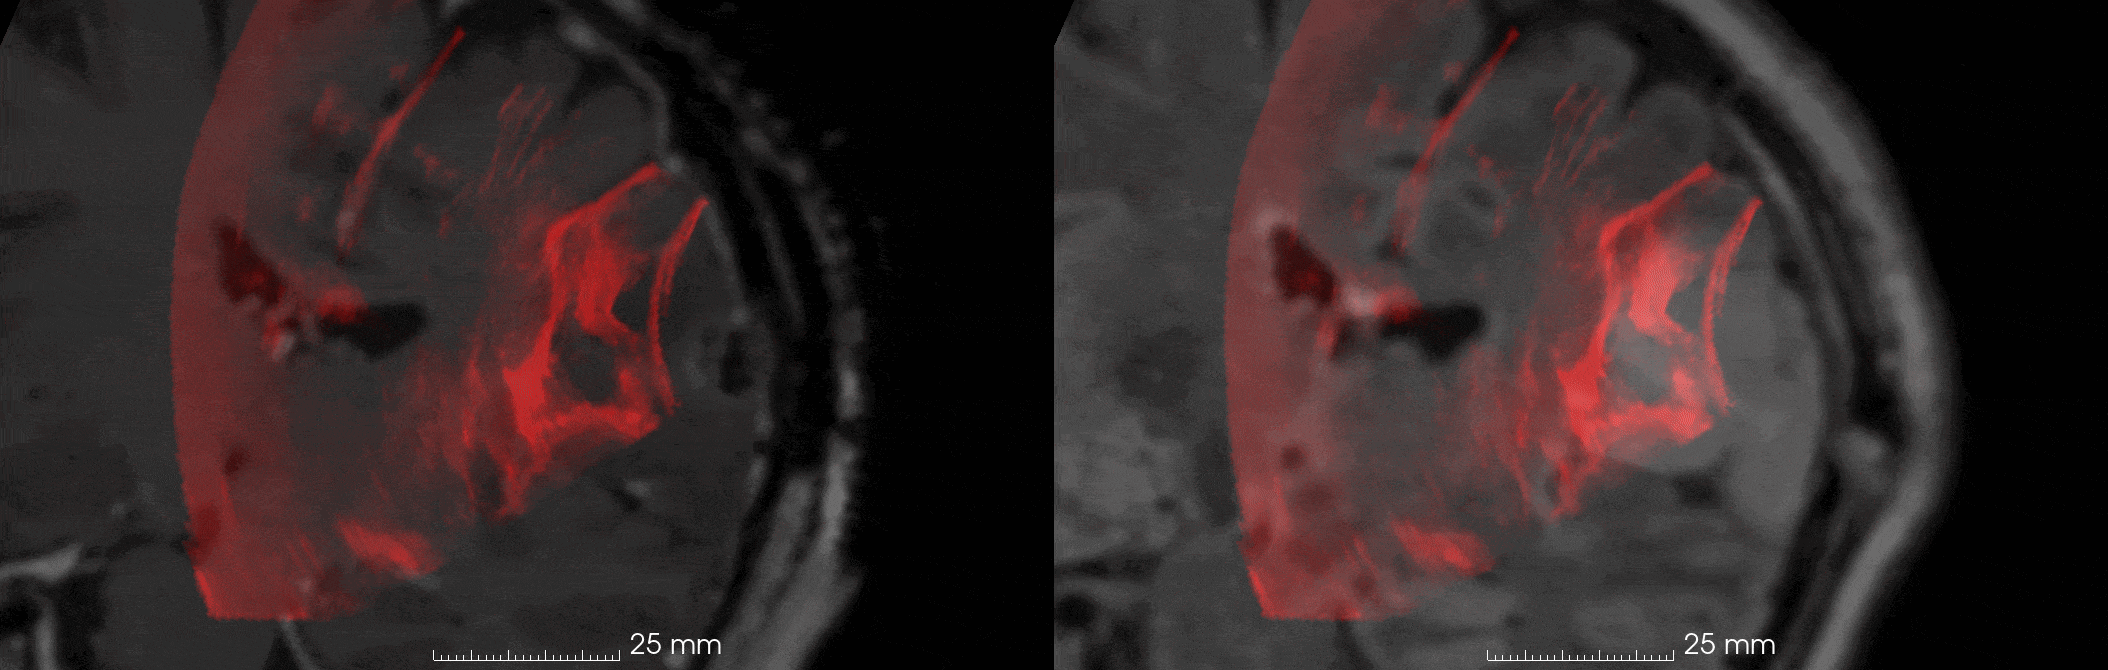

Figure 1: Illustrative example of unregistered preoperative MRI and overlaid post-resection iUS. Misalignment is observed between (a) contrast-enhanced T1 MRI and post-resection iUS, and (b) T2 MRI and post-resection iUS. A prominent resection cavity is clearly visible in the iUS images.